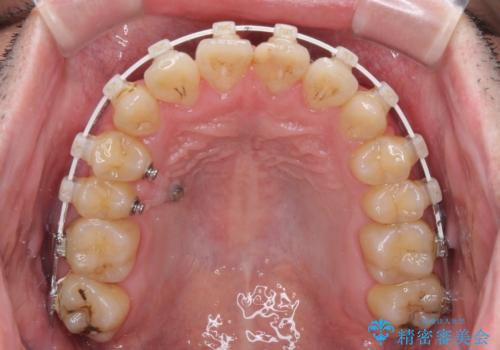

- 上下のデコボコと前歯のクロスバイトを改善したいとのことで来院された患者様です。

マウスピース矯正での自己管理には自信がないとのことで、ワイヤー装置による矯正治療を行うこととしました。

デコボコの程度は強かったのですが、口元の突出感はなかったため、非抜歯矯正としました。